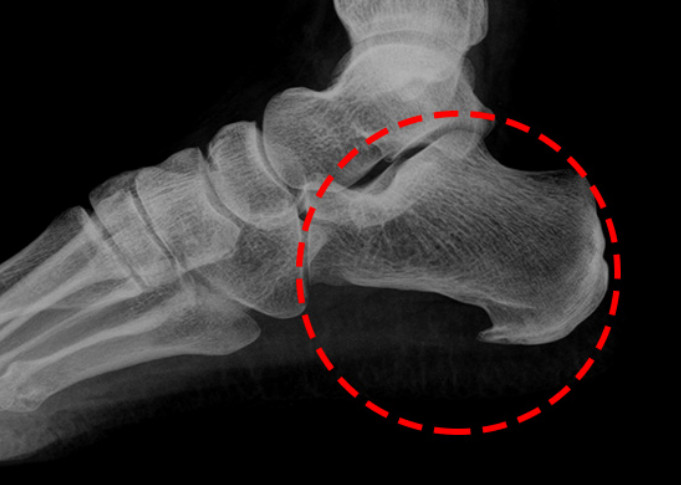

족저 근막염이란?

족저근막염이란 발바닥 뒤꿈치에 염증이 생기면서 나타나는 발바닥 통증을 일컫습니다. 이는 남성보다 여성이 2배 정도 많이 발병된다고 하는데, 그 원인은 과도한 발의 스트레스나 운동으로 인해 발병된다고 합니다. 이 밖에 몸무게의 급격한 증가나 평발도 발병 확률을 높이는 원인이 됩니다.

족저 근막염의 가장 흔한 증상으로는 아침에 통증이 매우 심하다는 점입니다. 그 이유는 밤사이에 족저근막이 수축되었다가 잠에서 깨서 일어나며 지면을 내딛는 순간 스트레칭 되면서 통증이 발생되기 때문입니다. 보통 원인은 종아리의 과단축으로 인하여 발바닥 근막이 당겨지면서 발병하는 경우가 대부분입니다. 때문에 족저 근막염을 예방하려면 평소 종아리와 발바닥을 같이 관리해 주어야 합니다. 만약 족저 근막염에 걸린 경우에는 생활 개선과 함께 필요에 따라 약물이나 의료적 치료가 병행되어야 합니다.